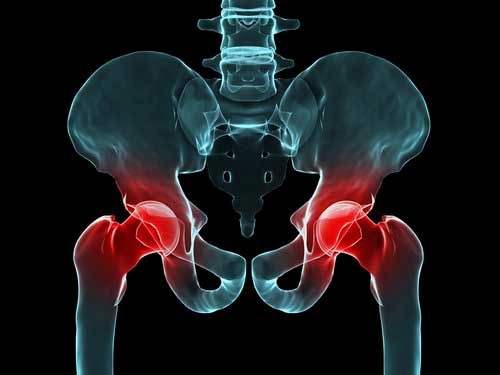

دررفتگی مادرزادی لگن زمانی رخ می‌دهد که سر گرد استخوان ران به‌درستی داخل حفره لگن (استابولوم) قرار نگرفته باشد. این مشکل ممکن است از لحظه تولد وجود داشته باشد یا در هفته‌های اول زندگی مشخص شود. در برخی کودکان سر استخوان ران کاملاً بیرون از حفره است و در برخی دیگر فقط شل و ناپایدار است. این بیماری در دختران حدود ۷ برابر بیشتر از پسران دیده می‌شود و معمولاً لگن چپ بیشتر درگیر می‌شود. اگر درمان نشود، با بزرگ شدن کودک، کوتاه شدن پا و درد شدید ایجاد می‌کند. تشخیص و درمان به‌موقع باعث می‌شود کودک زندگی کاملاً طبیعی داشته باشد.

درمان نشدن این بیماری باعث لنگش دائمی، کوتاه شدن پا، درد مزمن و آرتروز زودرس (حتی در سنین نوجوانی) می‌شود. کودک ممکن است نتواند مثل هم‌سن‌هایش بدود یا ورزش کند. در بزرگسالی احتمال نیاز به تعویض کامل مفصل لگن بسیار بالا می‌رود. حتی پس از درمان موفق هم باید تا سن بلوغ هر سال عکس و معاینه انجام شود تا از رشد طبیعی استخوان‌ها مطمئن شویم. پیگیری منظم مهم‌ترین عامل جلوگیری از عوارض دیررس است. خوشبختانه بیش از ۹۵ درصد کودکانی که به‌موقع درمان می‌شوند، زندگی کاملاً طبیعی خواهند داشت.